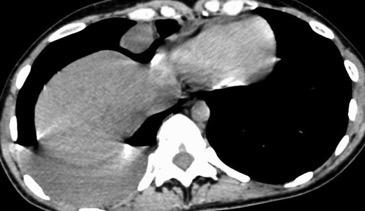

Naidich DP et al. Computed tomography of the diaphragm: peridiaphragmatic fluid localization.J Comput Assist Tomogr1983.

En el corte axial, el líquido pleural se sitúa por detrás

Quiste hidatídico.

Comunica con el hiato esofágico y el espacio pararrenal anterior.

Colecciones “inflamatorias” abdominales llegan al tórax vía el hiato esofágico o por vía transdiafragmática

Afectación transdiafragmática: 5,6-43,7% de quistes hepáticos. “Área desnuda” del hígado.

Panda A et al. “Straddling Across Boundaries”. Thoracoabdominal Lesions: Spectrum and Pattern Approach. Curr Probl Diagn Radiol. 2015 Área desnuda. El hígado en contacto directo con el tendón central del diafragma. Contiene el hiato de VCI.

Pedrosa I et al. Hydatid Disease: Radiologic and Pathologic Features and Complications. Radiographics 2000